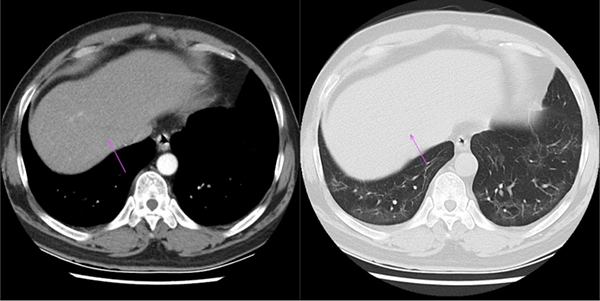

图:老康的CT片,肿物侵犯右侧膈神经,导致右侧膈肌抬高(箭头处)

图:老康的CT片,肿瘤下部侵犯右侧肺门区域,右肺支气管、血管受侵(箭头处)